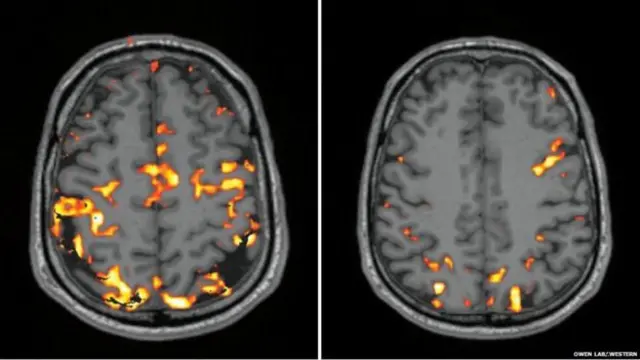

தமது மூளையில் என்ன நடக்கிறது என்பதை அறியும் ஆர்வத்தால், எம்.ஆர்.ஐ. ஸ்கேன் அறையில் இருக்கும்போது ஃபெர்குஸ் வால்ஷ் அறிவுத் திறன் சோதனைகளை செய்து பார்த்தார். வழக்கப்படி தூங்கிய இரவுக்குப் பிறகு ஒருமுறையும், போதிய உறக்கமில்லாத இரவுக்குப் பிறகு ஒருமுறையும் அறிவுத் திறன் சோதனைகளைச் செய்யும்போது எம்.ஆர்.ஐ. ஸ்கேன் எடுத்துக்கொண்டார். மூளையின் ரத்த ஓட்டத்தை அடையாளம் காணும் வகையில் எடுக்கப்பட்ட ஸ்கேன் அது. கூடுதலாக செயல்பட்டுக்கொண்டிருந்த மூளையின் பகுதிகளை ஆரஞ்சு வண்ணத் திட்டுகளாக ஸ்கேன் அடையாளம் காட்டியது.

நல்ல உறக்கத்துக்குப் பின்னும், போதிய தூக்கமில்லாத நிலையிலும் எடுக்கப்பட்ட ஸ்கேன்கள் பளீரென வேறுபாடுகளைக் காட்டின. தூக்கமின்மைக்குப் பிறகு தமது மூளையின் செயல்பாடு வெகுவாகக் குறைந்திருந்ததை ஃபெர்குஸ் வால்ஷின் கவனித்தார்.